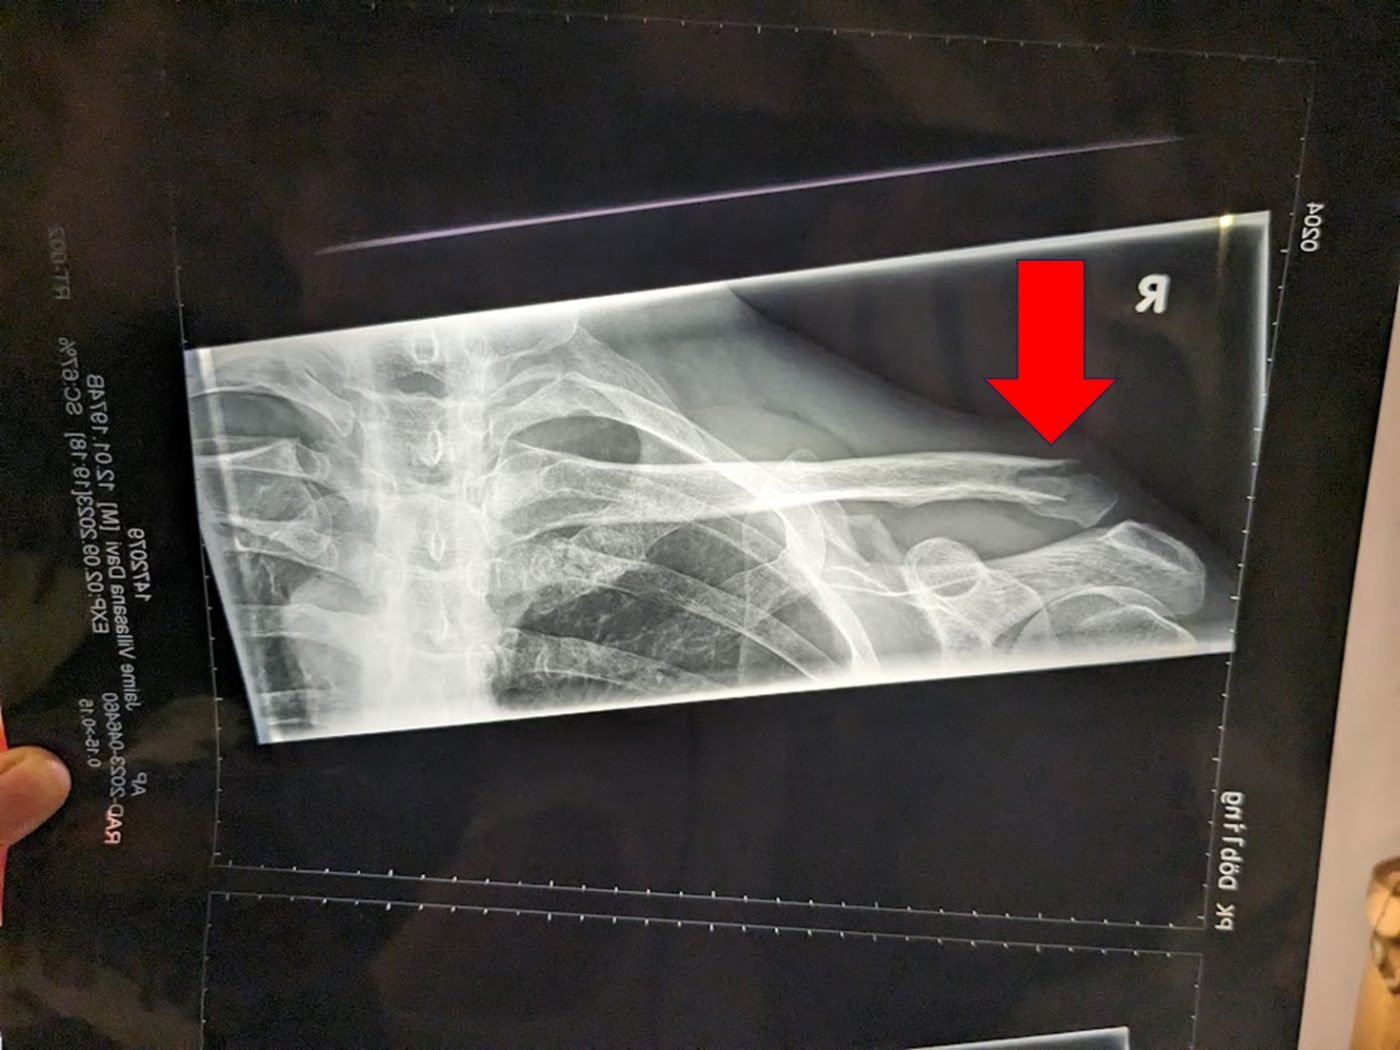

Llegué a emergencias de un hospital pequeño, me registré, tardaron algo en atenderme, supongo por ser sábado en la tarde/noche. Llega el doctor y me pregunta que me pasó, le explico. Me toma radiografía y me la muestra y me dice; es una fractura en clavícula como puedes ver cerca del hombro. Es simple y no múltiple, además no es expuesta. Tienes dos opciones: a) operar, significando una recuperación más pronta; b) usar banda porta brazo, tarda más en recuperar (hasta cuatro semanas). Le pregunto cuál es el estándar; me dice la banda porta brazo. Le digo quiero ello. Me recetó solamente pastillas para el dolor. Nada para lo inflamado. Esa noche tomé una pastilla para el dolor y aun con ella el dolor era algo intenso. Tomar baño fue complicado y dormir todavía peor. Paso la noche semi sentado en la cama debido al dolor.

Afortunadamente la fractura fue simple, más raspones y nada más. Imagen: Jaime VD.